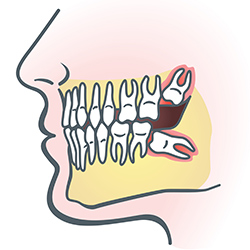

Wisdom teeth are types of molars found in the very back of your mouth. These teeth usually appear in late teens or early twenties but may become impacted (fail to erupt) due to lack of room in the jaw or angle of entry. When a wisdom tooth is impacted, it may need to be removed. If it is not removed, you may develop gum tenderness, swelling, or even severe pain. Impacted wisdom teeth that are partially or fully erupted tend to be quite difficult to clean and are susceptible to tooth decay, recurring infections, and even gum disease.

Wisdom teeth are typically removed in the late teens or early twenties because there is a greater chance that the teeth's roots have not fully formed and the bone surrounding the teeth is less dense. These two factors can make extraction easier, as well as making the recovery time much shorter.

In order to remove a wisdom tooth, your dentist first needs to numb the area around the tooth with a local anesthetic. Since the impacted tooth may still be under the gums and imbedded in your jaw bone, your dentist will need to remove a portion of the covering bone to extract the tooth. In order to minimize the amount of bone that is removed with the tooth, your dentist will often "section" your wisdom tooth so that each piece can be removed through a small opening in the bone. Once your wisdom teeth have been extracted, the healing process begins. Healing time varies depending on the degree of difficulty related to the extraction. Your dentist will share with you what to expect and provide instructions for a comfortable, efficient healing process.